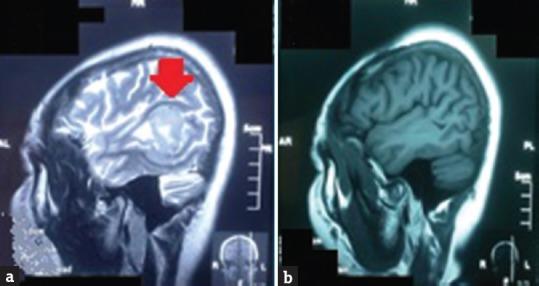

We report a rare case of a young female with primary brain fibrosarcoma, and to the best of our knowledge, we believe that only <50 cases have been reported or described worldwide so far. Fibrosarcoma is a malignant neoplasm, in which histologically the predominant cells are fibroblasts that divide excessively without cellular control and they can invade local tissues or metastasize. Primary central nervous system fibrosarcomas are very aggressive neoplasms and generally have a poor prognosis. This tumor is either from sarcomatous transformation of a meningioma or arises within the brain parenchyma. Our patient, a 48-year-old woman, who presented with progressive speech disorder over the period of 4 months, showed a left temporoparietal lesion with surrounding edema and local mass effect. Total surgical resection was achieved. Histopathology revealed classical fibrosarcoma features and secondary screening revealed no other distant lesion as diagnosis of primary brain fibrosarcoma was established. This case is deemed to be extremely rare because most reports claim that recurrence is within 6 months with poor prognosis; however, this patient is currently recurrence-free at 3 years. This would suggest of the possibility for a relook into this disease's course and recurrence rate when complete excision is achieved. Due to extreme rarity of these tumors, more comparative studies will be needed to improve the disease outcome.

我们报告了一例罕见的原发性脑纤维肉瘤年轻女性病例,据我们所知,到目前为止,全球仅报告或描述了不到50例。纤维肉瘤是一种恶性肿瘤,从组织学上看,主要细胞是成纤维细胞,它们不受细胞控制地过度分裂,可侵犯局部组织或发生转移。原发性中枢神经系统纤维肉瘤是极具侵袭性的肿瘤,通常预后较差。这种肿瘤要么是脑膜瘤的肉瘤样转化,要么起源于脑实质内。我们的患者是一名48岁女性,在4个月内出现进行性言语障碍,表现为左颞顶叶病变,伴有周围水肿和局部占位效应。实现了肿瘤全切。组织病理学显示为典型的纤维肉瘤特征,二次筛查未发现其他远处病变,从而确诊为原发性脑纤维肉瘤。该病例被认为极为罕见,因为大多数报告称复发在6个月内,预后较差;然而,该患者目前3年无复发。这表明在实现完全切除后,有可能重新审视这种疾病的病程和复发率。由于这些肿瘤极为罕见,需要更多的对比研究来改善疾病的治疗结果。